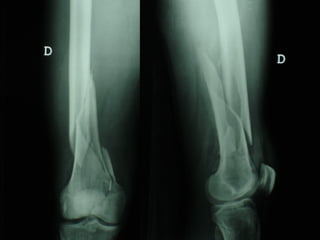

Dal Gennaio 2000 al Febbraio 2006 abbiamo trattato 167 fratture chiuse  con placca percutanea  in 164 pazienti :  27 lesioni diafisarie di gamba, 12 piloni tibiali ,  11 fratture prossimali di tibia, 36 fratture sovracondiloidee di femore, 17 fratture diafisarie di femore, 43 fratture metaepifisarie prossimali di omero, 21 diafisarie d’omero.  156 guarigioni 8 fallimenti

I buoni risultati ottenuti dipendono da 5 punti fondamentali:   una accurata riduzione percutanea della frattura  precise vie di accesso  l’utilizzo della placca che consenta il più lungo braccio di leva possibile il pretensionamento della placca  una sintesi con un ridotto numero di viti

Accurata riduzione percutanea della frattura

Precise vie di accesso

Placche lunghe e pretensionate

Placche lunghe e pretensionate Sintesi con un ridotto numero di viti